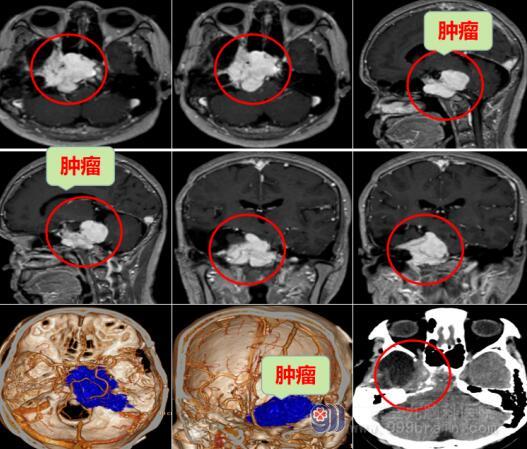

为寻求进一步治疗,雷女士来到广东三九脑科医院,神经外十科主任欧阳辉教授及李兴可主治医师接诊了她。进一步详细行头部MR检查提示:右侧岩斜区占位性病变,考虑脑膜瘤,病灶包绕邻近右侧海绵窦及右侧颈内动脉,邻近脑干、右侧桥臂及局部小脑半球仍明显受压。

完善相关检查后,为患者行右侧岩斜区脑膜瘤切除术,术中利用高清显微镜、神经电生理检测等先进设备,手术历时约9个小时。现雷女士恢复可,手脚活动灵活。术后病理提示:脊索样脑膜瘤,WHO II级。